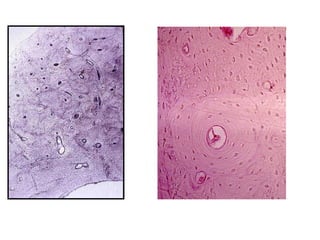

HUESO LAMINILLAR COMPACTO

Hueso compacto: Tipos

de sistemas Laminillares

• Circunferencial externo

• Circunferencial Interno

• Haversianos

• intersticiales

Lagunas

Endostio

Hueso Laminillar Esponjoso

Hueso No-Laminillar:

Hueso inmaduro